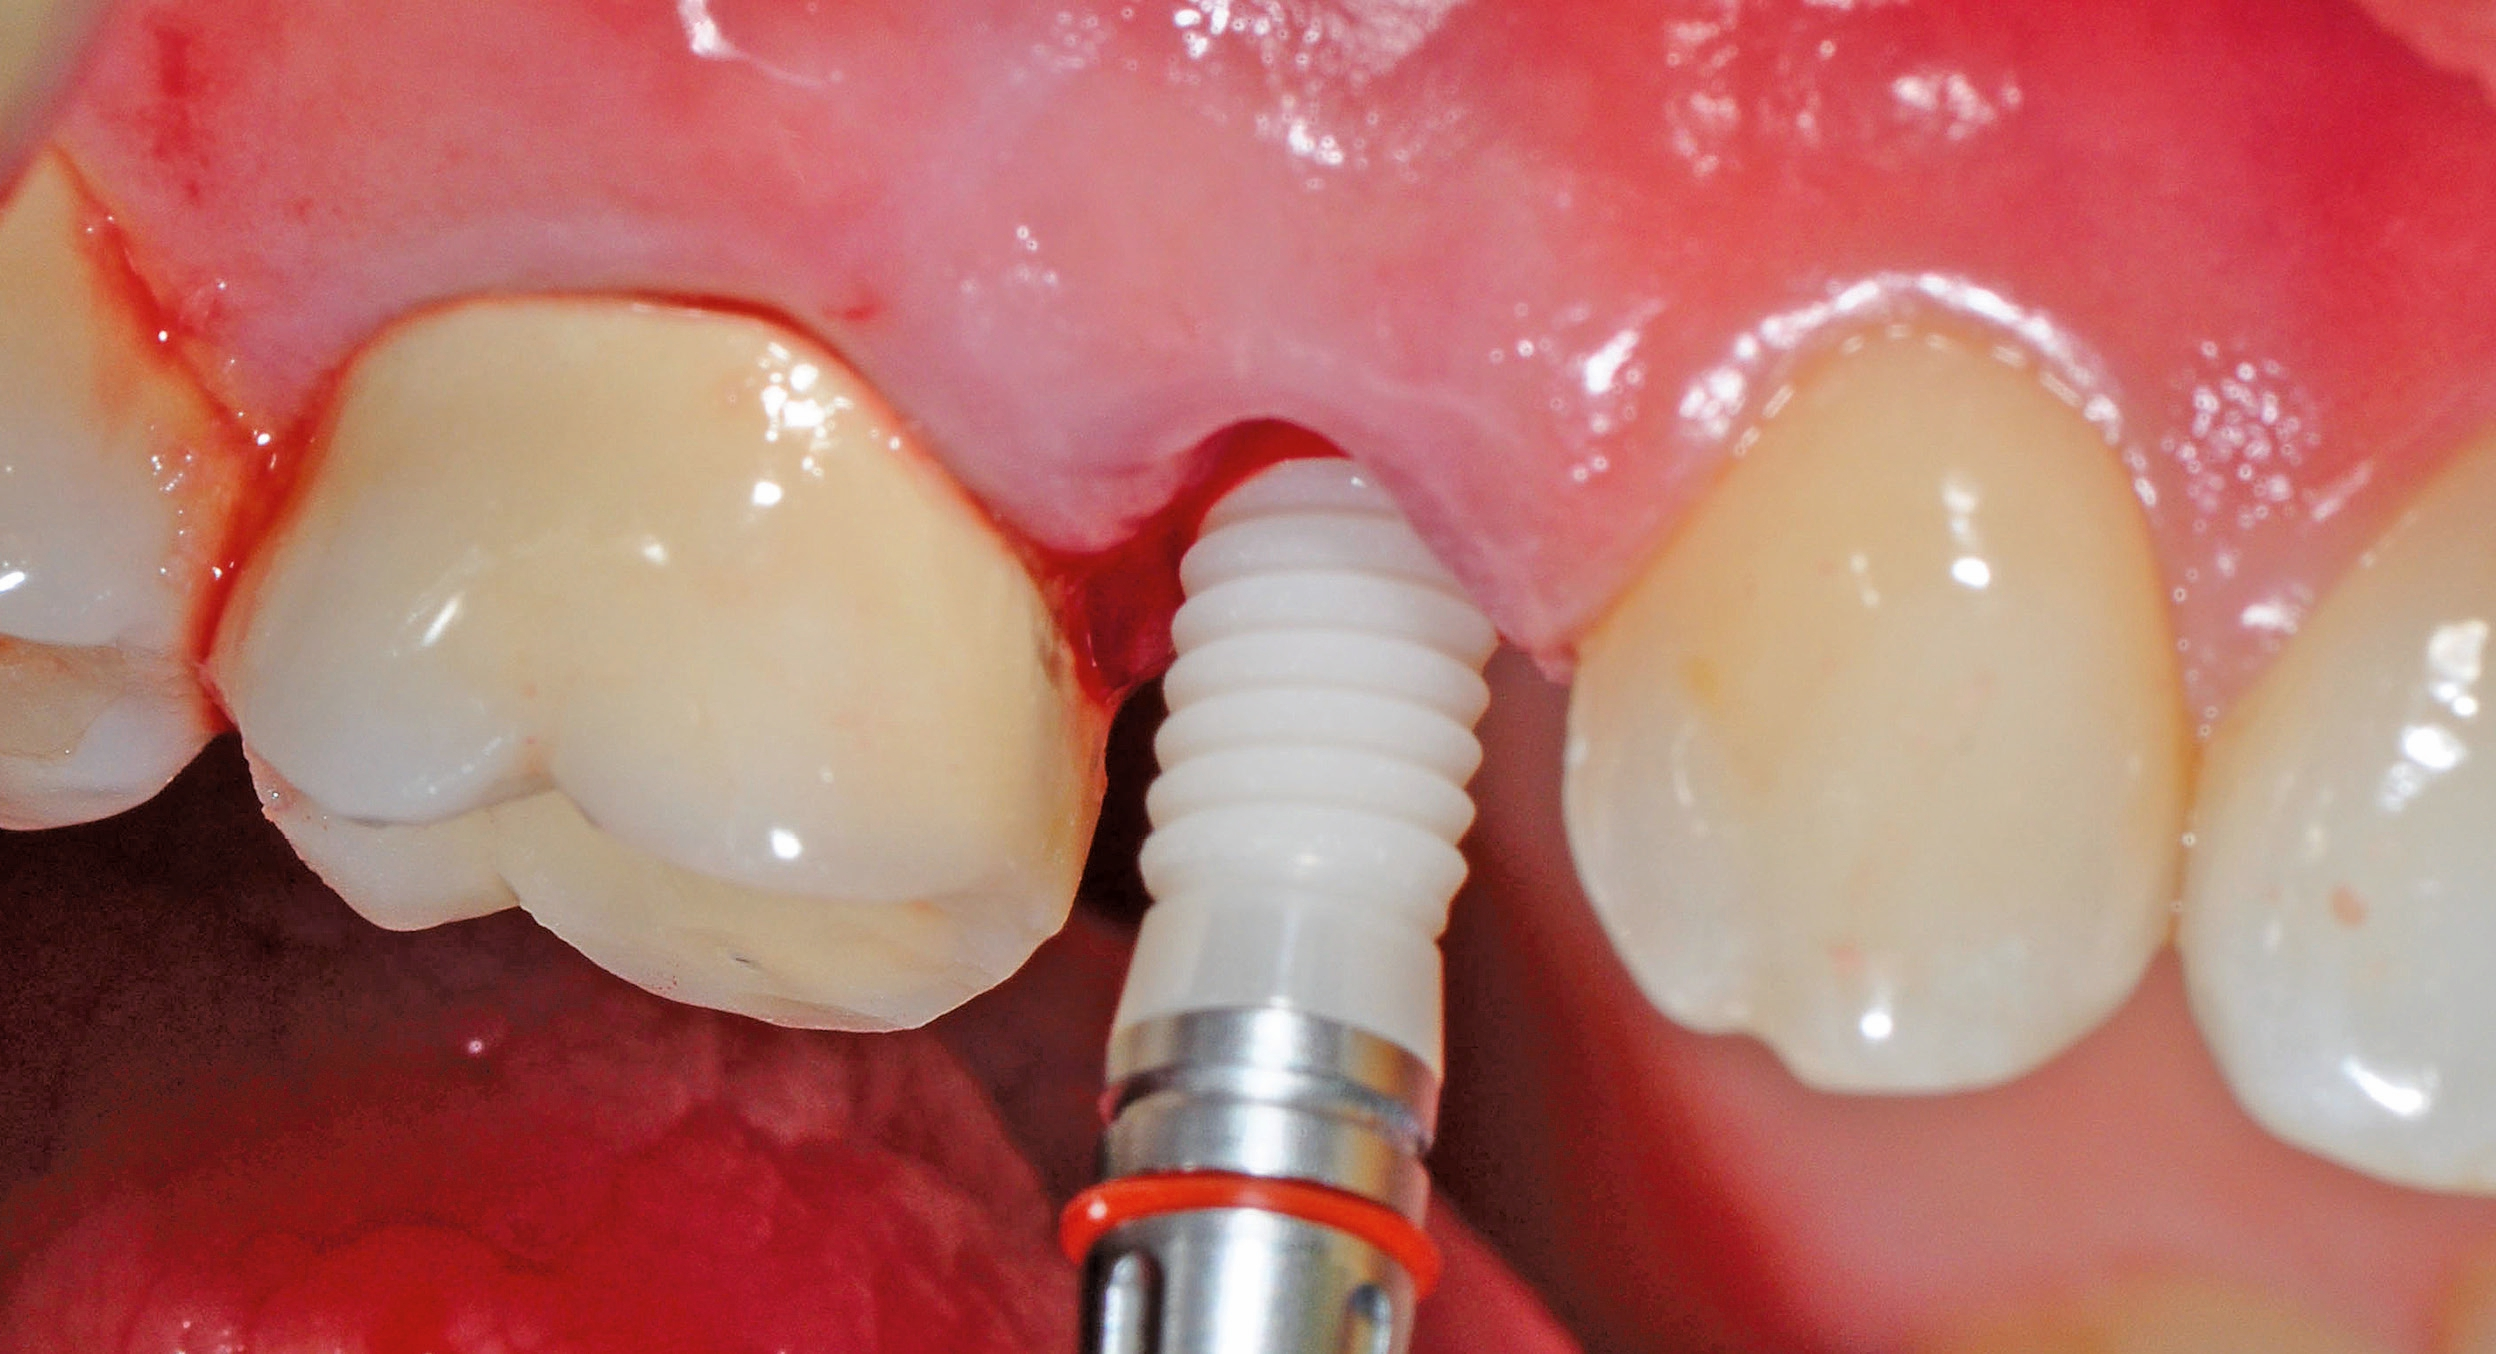

Implantatinsertion

Nach sorgfältiger Kürettage und Inspektion einer idealen Knochenalveole vom Typ I [11] konnte mit der Sofortimplantation begonnen werden. Die ersten beiden Pilotbohrungen wurden teilnavigiert mit der Bohrschablone durchgeführt. Das restliche Bohrprotokoll wurde nach den Vorgaben des Herstellers frei durchgeführt. Mit der Insertion des Implantats konnte die nötige Primärstabilität von 35 Ncm für eine sofortige provisorische Versorgung erreicht werden. Im Vorfeld war ein Situationsmodell der Ausgangssituation und darauf eine Tiefziehschiene vorbereitet worden, die jetzt für die intraorale Herstellung des Provisoriums mit fließfähigem Kompositmaterial verwendet wurde. Als stabilisierende Gerüststruktur diente dabei die präzise sitzende Einbringkappe (insertion.transfer) auf dem Implantatkopf, die zuvor auf die entsprechende Höhe eingekürzt worden war. Nach der Ausarbeitung und okklusalen Adjustierung der Krone wurde diese provisorisch zementiert.